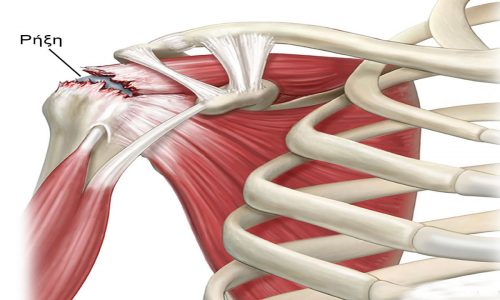

Η ρήξη του στροφικού πετάλου δύναται να είναι οξεία ή χρόνια, να αφορά σε ένα ή περισσότερους τένοντες και να είναι πλήρης ή μερικού πάχους. Οξεία ρήξη παρατηρείται σε περιπτώσεις τραυματισμού, σε νέους συνήθως μετά από πτώση ή σε μεσήλικες μετά από εξάρθρημα του ώμου. Χρόνια ρήξη συναντούμε κυρίως σε μεγαλύτερες ηλικίες και οφείλεται στη βαθμιαία φθορά και εκφύλιση των τενόντων.

Τα συμπτώματα της ρήξης είναι κυρίως πόνος στον ώμο που δύναται να αντανακλά στη μεσότητα του βραχίονα και αδυναμία στην απαγωγή ή τις στροφικές κινήσεις σε διάφορο βαθμό, ανάλογο της ρήξης. Αρχικά πόνος υπάρχει στην κίνηση του βραχιονίου πάνω από το οριζόντιο επίπεδο του ώμου, ενώ σταδιακά γίνεται πιο συχνός και έντονος με νυκτερινή μάλιστα παρουσία.